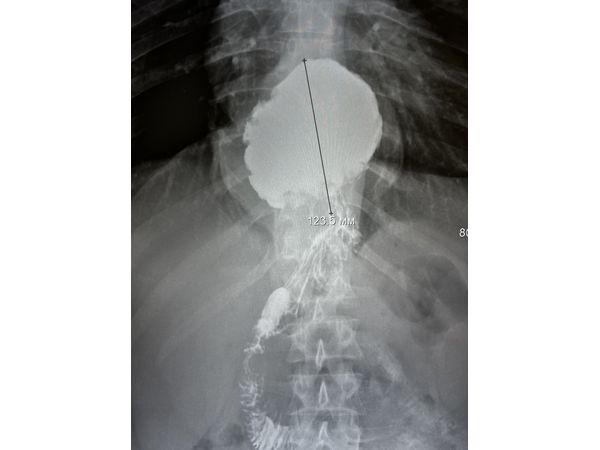

Вместо гастроскопии сделали рентгеноскопическое исследование пищевода, желудка и двенадцатиперстной кишки. По результатам удалось установить, что часть желудка расположена в грудной полости и зафиксирована в заднем средостении (между сердцем и позвоночником). Такое состояние соответствует фиксированной аксиальной кардио-фундальной грыже пищеводного отверстия диафрагмы.

Через месяц провели рентгенконтроль: грыжи не было, желудок расположен правильно (в брюшной полости). Гастроэзофагеального рефлюкса в положении Тренделенбурга (лёжа на спине, ступни немного выше головы) и стоя не выявлено.